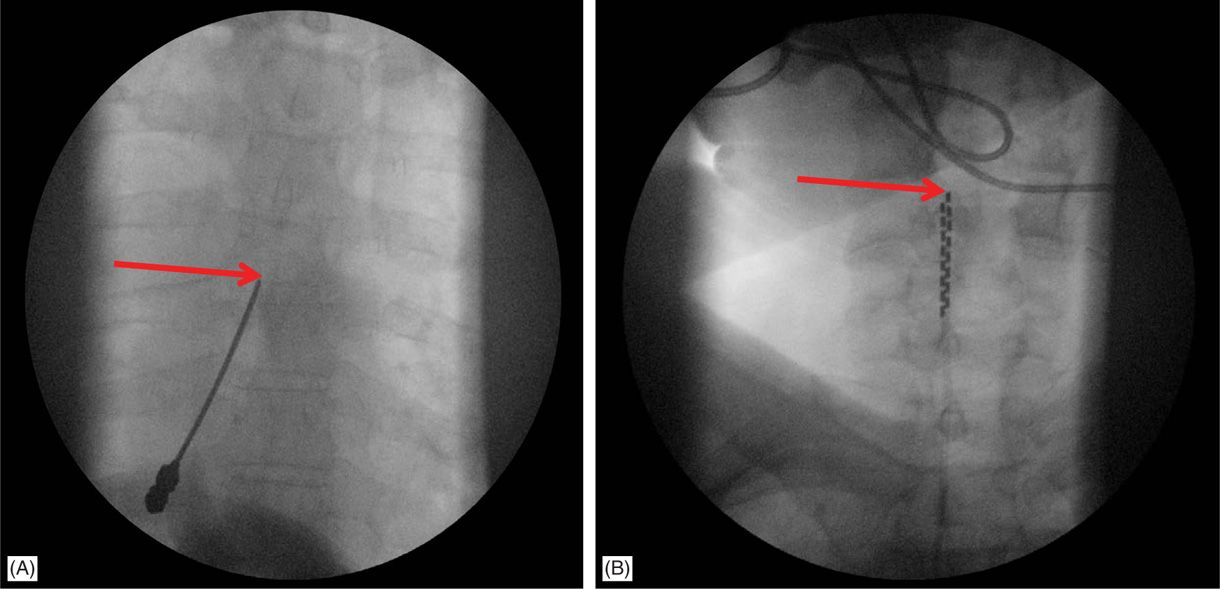

Scs Implantation - Spinal Cord Stimulation: Implantation Techniques / Scs involves percutaneous or surgical implantation of electrodes in the epidural space, with power supplied by an implanted battery.

Scs involves percutaneous or surgical implantation of electrodes in the epidural space, with power supplied by an implanted battery. While scs is meant to be a permanent implant, there are cases where the device . Successful permanent scs implant was defined . If your spinal cord stimulation trial was successful, you may be eligible to have a scs system permanently implanted to reduce and manage . Neuromodulation with scs starts with a trial phase.